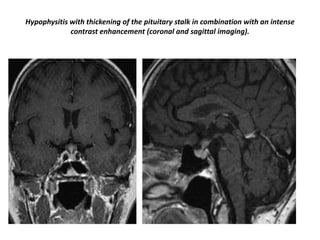

Hypophysitis with thickening of the pituitary stalk in combination with an intense

contrast enhancement (coronal and sagittal imaging).